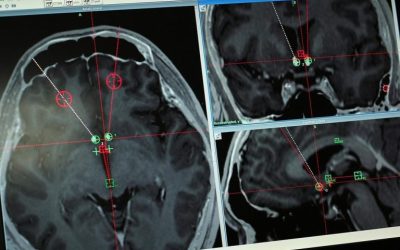

Nouvelle étude sur la santé cognitive des aînés

MONTRÉAL — Des chercheurs canadiens recrutent 350 aînés, dont une soixantaine au Québec, pour participer à un programme en ligne afin d’accroître leurs connaissances sur les troubles neurocognitifs et d’améliorer leurs habitudes de vie. Le programme Santé Cerveau...